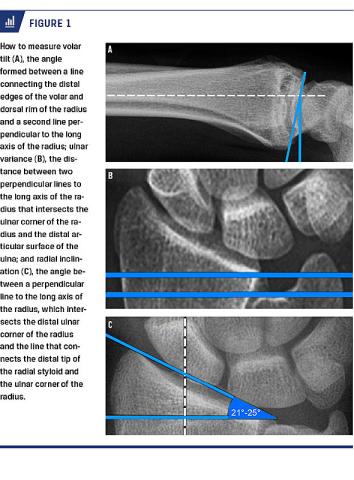

In order to help the surgeon to decide on optimal treatment, it is commonly accepted to use four to five different measurements on radiographs to investigate how severe the fracture appears. Those typically used are volar/dorsal tilt, radial inclination, ulnar variance and intraarticular step-off [5]. Currently, a common treatment option for unstable distal radius fracture is open reduction and internal fixation with a volar locking plate [6, 7]. Some authors have argued that volar plates are better than other methods at restoring and maintaining the anatomy of the distal radius [8].

A consultant of radiology, an orthopaedic consultant and an orthopaedic intern evaluated dorsal or volar tilt, ulnar variance (> 2 mm), radial inclination (< 21° or > 25°), radiocarpal joint step-off (> 2 mm) and distal radioulnar joint incongruity on standard anteroposterior and lateral projections of the injured distal forearm obtained preoperatively and five weeks post-operatively. Furthermore, perioperative fluoroscopic imaging of anteroposterior lateral projections was assessed. The continuous variable (volar tilt) was based on the average of measurements performed by the three independent observers. In cases of disagreement on dichotomous variables (yes/no), the majority of the three observers was defined as the truth. No consensus meeting was held throughout the study. However, before the study was commenced, all observers were given guideline illustrations of how to evaluate the variables according to Figure 1.